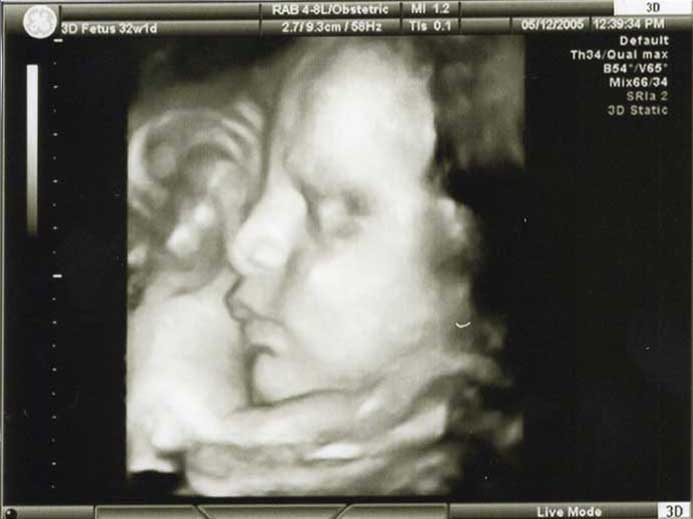

3D/4D HD LIVE

Στο ιατρείο μας προσφέρουμε υψηλής ευκρίνειας 3D και 4D τεχνολογία απεικόνισης του εμβρύου. Η τεχνολογία αυτή αποτελεί ένα ακόμα σημαντικό διαγνωστικό όπλο στη φαρέτρα του προγεννητικού ελέγχου, ενώ ταυτόχρονα ενισχύει την ανάπτυξη του δεσμού ανάμεσα στους μελλοντικούς γονείς και το μωρό τους.